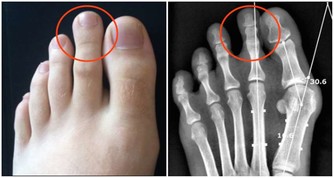

因為糞便大多在左側的結腸成形,因此如果阻塞的狀況嚴重的話,所排出的糞便就 會有時還會參雜血絲, 嚴重到便祕及解血便情形。

若無便祕,每次如廁後應注意糞便顏色與形狀,及是否有血絲等異常狀況。